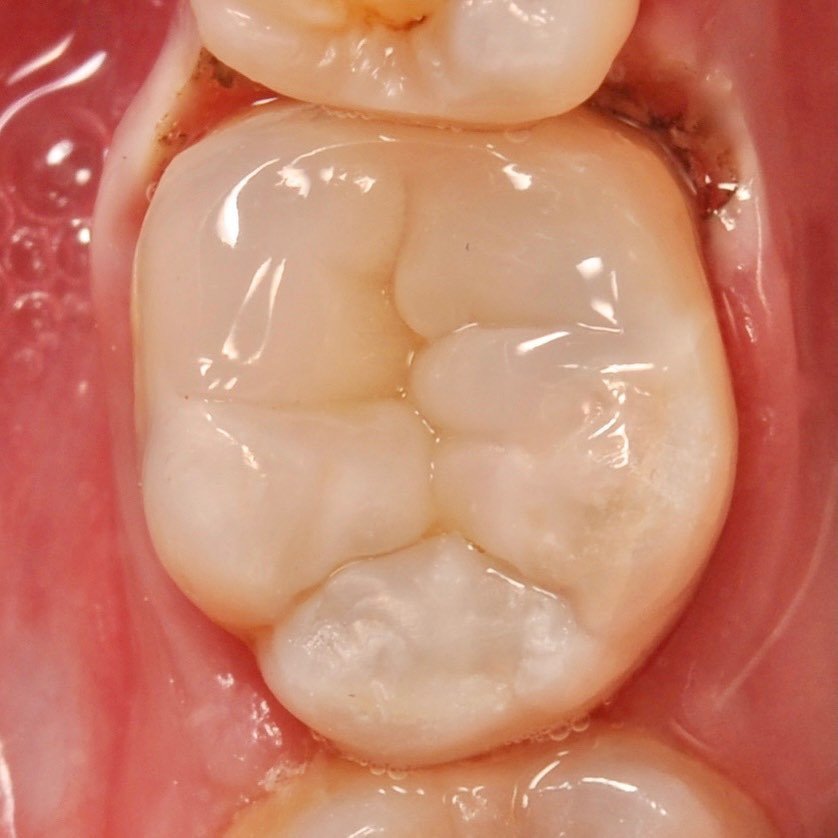

The use of a microscope in dentistry is an ultra-modern direction. Optical instruments allow for constant monitoring of the treatment process, which directly affects the quality of treatment and is aimed at preserving tooth tissues.

The microscope illuminates and enlarges the working field by about 25 times, which helps to accurately determine the anatomical structure of the tooth and restore it with maximum accuracy.

• Using a microscope, you can determine the lines of cracks and fractures on the tooth.